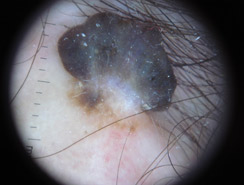

Dermatoscopia

Lo studio e la diagnosi delle neoformazioni cutanee attraverso strumenti specifici indicati per un'analisi delle caratteristiche strutturali superficiali e profonde delle varie neoformazioni cutanee: dermatoscopia, dermalite a luci fotocromatiche, mappatura nevica con videodermatoscopia digitale.

Al fine di una corretta diagnosi dei nevi, e dunque di un'efficace prevenzione da forme tumorali, è indispensabile visionare in profondità i caratteri di ogni formazione nevica. Ciò è reso possibile dall'utilizzo del dermatoscopio e dalla concomitante mappatura nevica, con l' eventuale rimozione chirurgica o laser di: